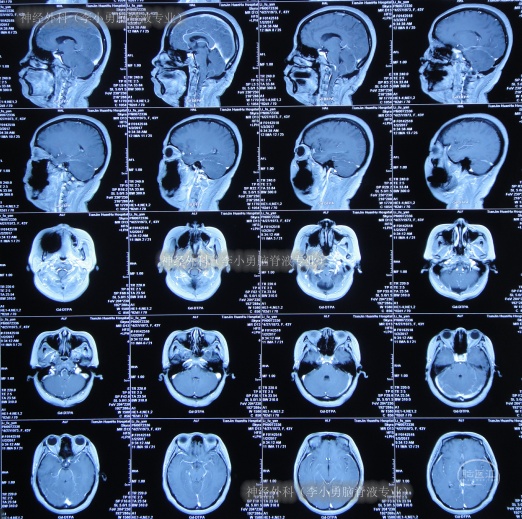

患者从2006年左右开始出现间断头痛反应,尤其在咳嗽、哭笑时头痛加重,一直保守治疗,间断头痛十余年后即2016年10月23日,头痛症状加剧实在无法忍受,就诊于天津市某区医院,查头颅CT(图-1)后怀疑是小脑扁桃体下疝,建议进一步检查。在神经外科(李小勇脑脊液专业)治疗过程和结果】

图-1:2016年10月23日头颅CT